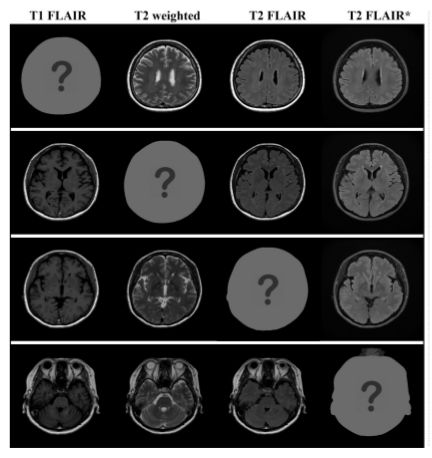

文章主要在三个数据集下进行实验测试,MR contrast synthesis 数据集是通过多动态多回波序列和来自 10 个受试者的附加 T2 FLAIR(流体衰减反转恢复)序列扫描总共 280 个轴脑图像。

在数据集中有四种类型的 MR 对比图像:T1-FLAIR (T1F),T2-weighted(T2w),T2-FLAIR (T2F) 和 T2-FLAIR (T2F)。前三个对比度是从磁共振图像编译(MAGiC,GE Healthcare)获得的,T2-FLAIR * 是通过第三对比度(T2F)的不同MR扫描参数的附加扫描获得的。MR contrast synthesis 数据集也是作者进行本次研究的目的性数据集。

在 MR 的数据集上,实验对比了 CycleGAN、StarGAN 和 CollaGAN:

从医学分析上 T2-weighted 图像中的脑脊液(CSF)应该是明亮的,上图中的第二行结果,这个在 CollaGAN 上效果最佳,在 StarGAN 和 CycleGAN 上则是暗淡的,在另外两个数据集下的定性测试上,CollaGAN 也展示优势: